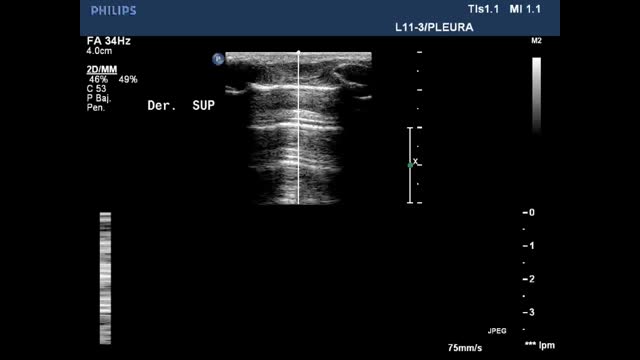

Once the two-dimensional image has been obtained, a study in M mode is performed that is essential for diagnosing normal lung, pneumothorax and pleural effusion.

Sinusoid sign (Suppl. Fig. 8) (Video 11): This is a dynamic sign. In M mode it manifests as a sinusoid, reflecting the variation of the interpleural distance with the respiratory movements. In this regard, the distance is shorter during inspiration, while in expiration the two pleural layers are more separated. When the fluid is more viscous or shows septation, this sign may be absent.